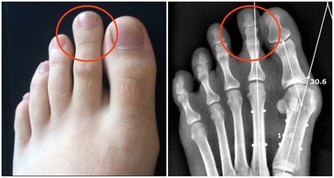

4、血管疾病。有些血管疾病比如常見於青年女性的雷諾病、大動脈炎,多發於中年男性的血栓閉塞性脈管炎,會影響人體末梢部位的供血。